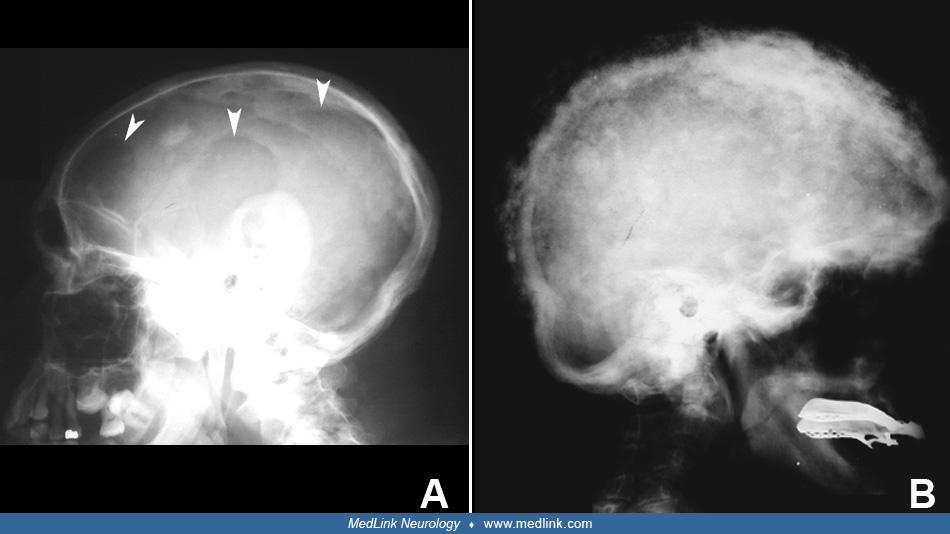

From www.medlink.com

Paget disease of bone neurologic complications MedLink Neurology Paget's Disease Complications A deadly complication of paget disease is the development of pagetic sarcoma, a tumor that can be fatal. It can cause bone pain, deformity,. Paget's disease can cause pain, deformity, fracture, osteoarthritis, neurological problems and rare complications. Paget's disease is a chronic condition that affects the skeleton and causes abnormal bone remodeling. It can lead to pain, deformity, fractures, and. Paget's Disease Complications.